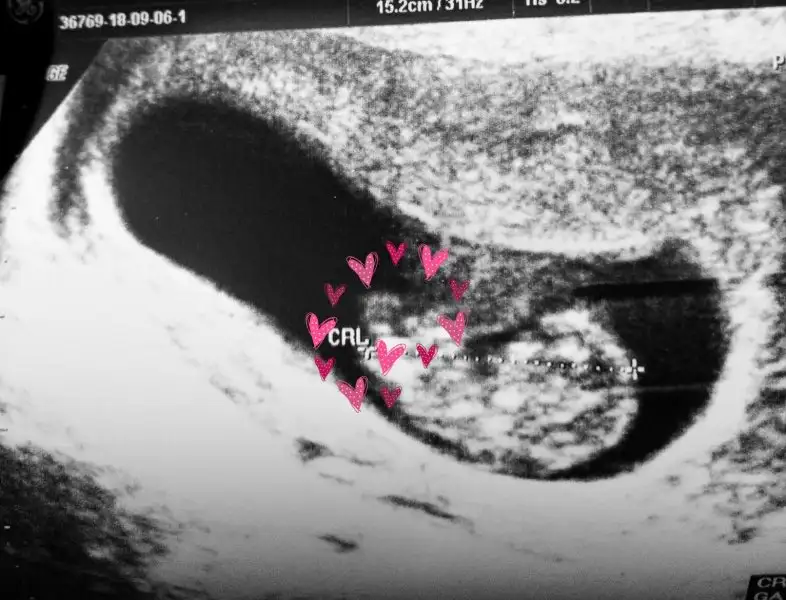

Biz de çok şaşırdık görünce.keseyi görmüştüm daha kalp atışını duymamıştım.Deniz atı gibi kuyruklu bir minik gorurum zannediyordum halbuki, ayağı mi çıkmış onun dedim ekrana bakincaAy resmen minik bir ayak var oradamaşallah

Geçmiş olsun canım. Bebişede maşşallahMerhaba arkadaşlar.Bayadir yazamıyorum.Okuyup çıkıyorum bazen birkaç sayfa.Babam kaza geçirdi bendeydi.Oglum hasta oldu hala tahlil vs için gidip geliyoruz.Bu arada bulantı devam ama kusmuyorum. En son 9+1 de gördük ve ilk kez kalp atışını dinledik çok şükür bir sorun yok Ayaklarını bile görmüştük nokta kadar parmakları bile vardifotografi yukleyebilirsem göreceksiniz siz de.boyu da 2.47 cm idi.Simdi 28 Eylül de ikili testimiz var.Sizler nasilsiniz bakalim Niye ben fotoğraf yukleyemiyorum yaa

Evet gorunuyor ayagi masallah cok tatliAh işte olduuubakın 9+1 yaşında bir minnagin ayacigina Bu arada doktorumuz 28 Eylül de cinsiyeti söylerim dedi, kendimi zor tutuyorum birşeyler almamak icin son kontrolde kuyruk tamamen yok olmuştu bu arada.

Merhaba arkadaşlar.Bayadir yazamıyorum.Okuyup çıkıyorum bazen birkaç sayfa.Babam kaza geçirdi bendeydi.Oglum hasta oldu hala tahlil vs için gidip geliyoruz.Bu arada bulantı devam ama kusmuyorum. En son 9+1 de gördük ve ilk kez kalp atışını dinledik çok şükür bir sorun yok Ayaklarını bile görmüştük nokta kadar parmakları bile vardifotografi yukleyebilirsem göreceksiniz siz de.boyu da 2.47 cm idi.Simdi 28 Eylül de ikili testimiz var.Sizler nasilsiniz bakalim Niye ben fotoğraf yukleyemiyorum yaa

Yaaa ama maşallahhhAh işte olduuubakın 9+1 yaşında bir minnagin ayacigina Bu arada doktorumuz 28 Eylül de cinsiyeti söylerim dedi, kendimi zor tutuyorum birşeyler almamak icin son kontrolde kuyruk tamamen yok olmuştu bu arada.

Ayy maşallah ya baya meydana çıkmış Allah sağlıkla nasip etsin. Bugün benimde randevum var ama benimki böyle görünmez herhalde doktorun ultrason cihazı berbatAh işte olduuubakın 9+1 yaşında bir minnagin ayacigina Bu arada doktorumuz 28 Eylül de cinsiyeti söylerim dedi, kendimi zor tutuyorum birşeyler almamak icin son kontrolde kuyruk tamamen yok olmuştu bu arada.